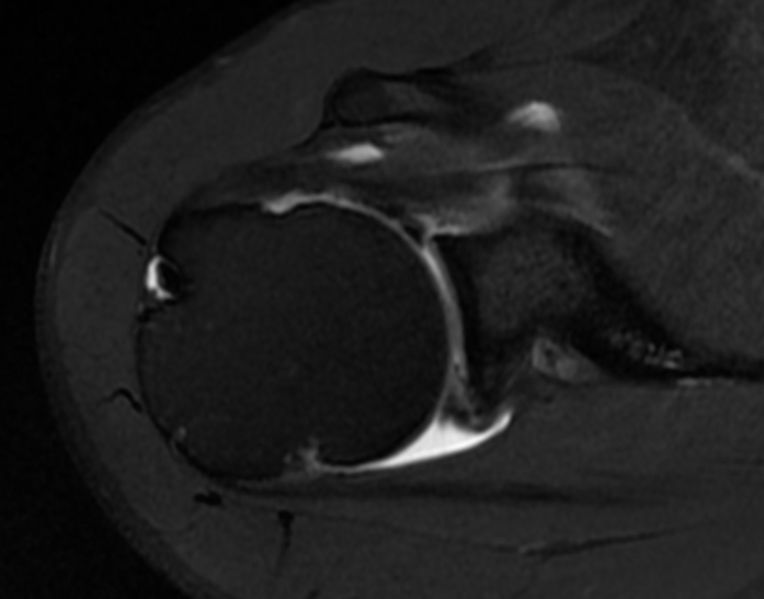

Axial T1 fat saturation magnetic resonance arthrography (MRA) sequence revealing humeral head cysts and a posterosuperior labral lesion.